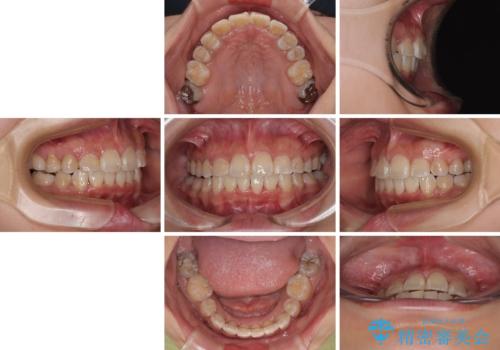

- 上下前歯のデコボコを気にして来院された患者様です。

上顎は両側の犬歯が骨内に埋伏しており、乳歯が残存している状態でした。

歯肉内に埋もれている場合には牽引することも可能ですが、両歯ともに骨内に完全に埋もれていたため、牽引することは不可能と判断しました。

口元の突出感があるわけではなく、叢生の程度もシビアではありませんでしたが、顎骨が小さく、左右ともに最後臼歯が歯肉に埋もれているため、下顎は左右第二小臼歯を抜歯することとしました。

上顎は左右ともに残存している乳歯を抜歯し、上下歯列を整えることとしました。

下顎は第二小臼歯を抜歯したため、治療期間が長期化すると思われましたが、大臼歯が後方に傾斜していたため、容易にスペースを閉じることができ、2年強で治療を終えることができました。